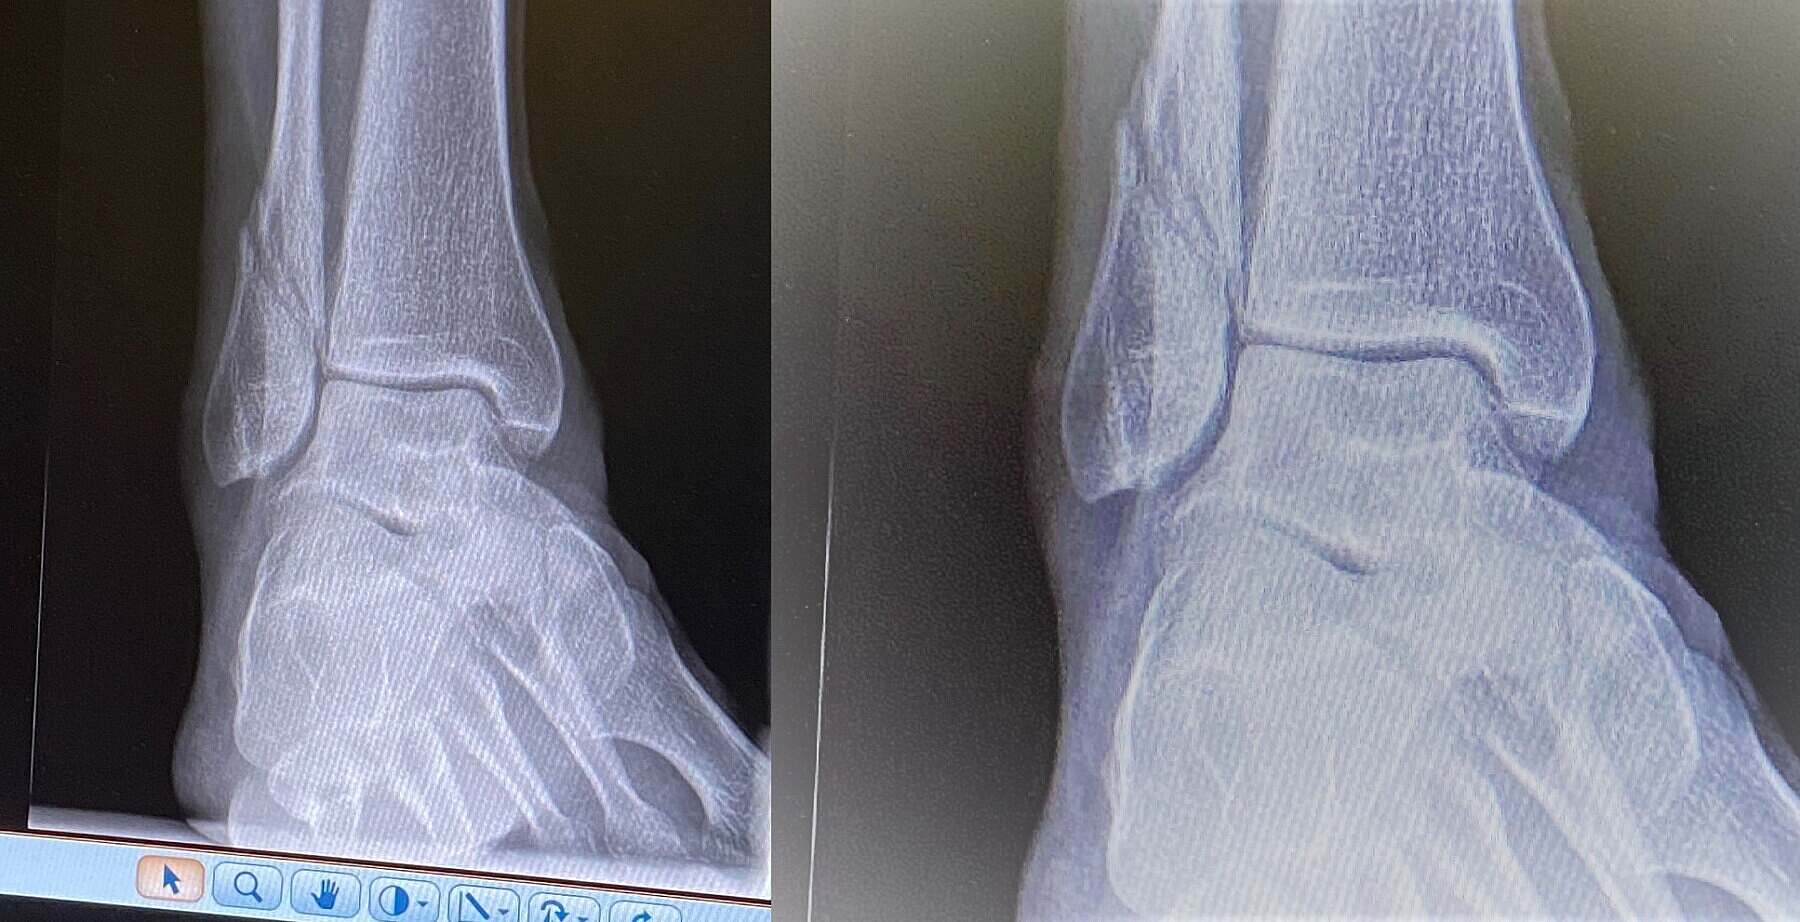

I walked in for an x-ray at the wonderful UCH fracture clinic last week and was met by "it's you!"

The radiologist was on duty the first time I checked into UCH at Easter time. She remembered because I was carrying my large Timbuk bag over my shoulder and Airnimal folding bike tucked under one arm. When the original x-ray popped out the machine I remember there was much gasping and then scrabbling for a wheel-chair and a generalised hurry to get me off my feet, well my right one at least. In truth I wasn't in a huge amount pain, certainly not as much as the doctors and radiologists assumed. But I had kind of suspected something was wrong as I couldn't plantar-flex that foot (i.e. go up on my toes). It wasn't pain blocking the movement, it was more that I could no longer propriocept the movement pattern.It was all written in neon if I had paused to read it. I couldn't organise the movement because the fibula was snapped in two. The x-ray above is the most recent and shows clear healing in the shaft of the fibula. it feels much better and the 5-6 weeks in the orthopedic boot have worked their magic by effectively freezing the foot in place 24 hours a day. It has served to remind me of the first principle of medicine - that the body heals itself. The role of the clinician is to put the body in a position and place where healing and rehabilitation can occur. And in that regard UCH have been incredible - checking on me every couple of weeks and taking progressive x-rays. I am now allowed to take the boot off periodically through the day, which feels amazing. I can now send the mental mapping to elevate onto my toes, but no longer have the strength to do so because I have lost 50% of my calf mass in six short weeks. Atrophy is just pitiless.